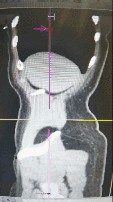

◈ 2022年8月26日,患者突发腹部疼痛。急诊行腹部CT检查提示:盆腔见较大不规则形混杂密度影,与双侧附件及邻近肠管、右侧髂血管分界不清,最大层面约13.4cm×11.8cm,其内密度不均,可见片状高密度影及钙化密度影,病变周围似见稍高密度包膜影。左上腹部小肠旁见肿块影,与局部肠管分界不清,局部肠管走行紊乱,管壁似欠连续,腹腔内见较多液体密度影及游离气体密度影。网膜略增厚。

2022年8月26日 腹部CT

◈ 检查结论:1、盆腔占位病变,对比2022-07-15片似变大,建议进一步检查。2、腹腔游离气体、考虑消化道穿孔,左上腹部小肠旁占位性病变,3、腹腔积液,对比前片积液量减少,网膜略增厚。